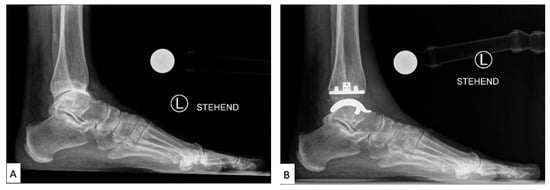

Figure 3. Labeled X-ray of (A) preoperative and (B) TAA implant performed on a patient, consisting of a polyethylene tibial component and metallic talar component [].

TAA was developed as a method of reducing pain while also preserving the mobility of the joint. Early first-generation TAA implants (Figure 3) consisted of two components: a concave tibial component composed of polyethylene and a convex talar component composed of metal alloy, both fixated with bone cement. However, early TAA implants are still associated with a high rate of failure, which has been attributed to permanent deformation of the polyethylene component, large bone resection to allow for cement fixation and loosening of the talar component due to the high strength of the talus bone [,,,].